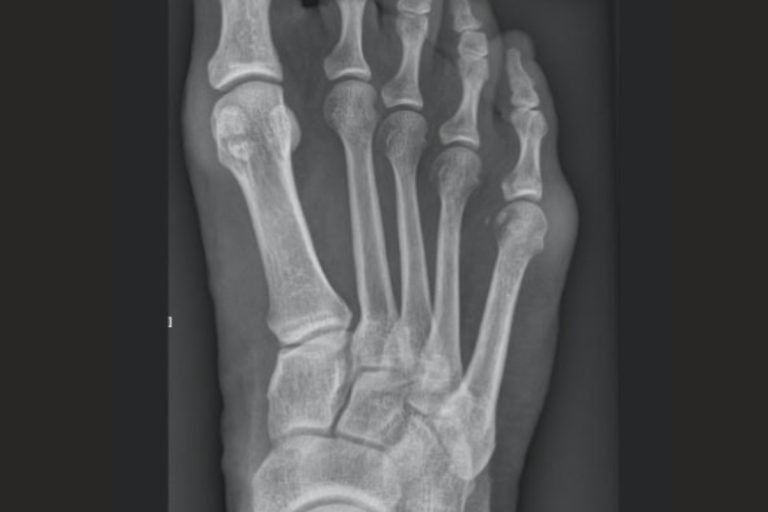

Badaniem decydującym w diagnostyce palucha sztywnego jest RTG stopy w obciążeniu, które pozwala ocenić stopień zwężenia szpary stawowej, obecność osteofitów oraz zaawansowanie zmian zwyrodnieniowych stawu. Obraz radiologiczny umożliwia określenie stadium choroby, co ma kluczowe znaczenie przy wyborze metody leczenia.